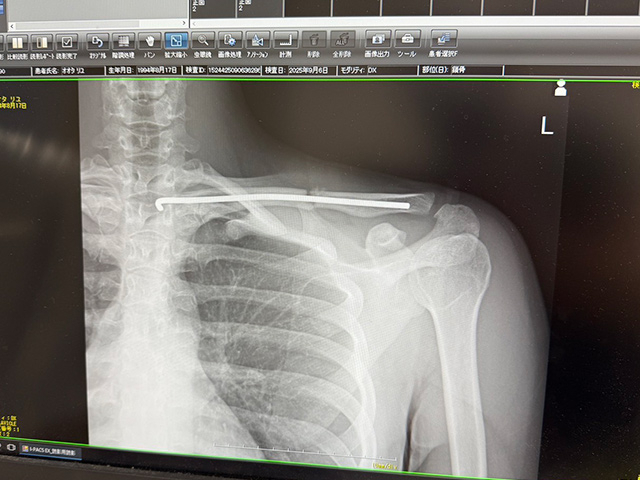

結論から言うと、いまだに骨は繋がっていません(-▽-;)!! 「完治」となると最低でも4か月から半年はかかるみたいですね。現状は手術をして、(折れている部分を)ワイヤーで繋げています。

ワイヤー越しに骨折箇所がはっきりとわかる状態(写真:著者提供)

痛みは日々弱くなっているけど、刺激が強い日はジンジン痛みます( ノД`)  あと、立ち漕ぎの瞬間も痛みが走りますね(>_<)